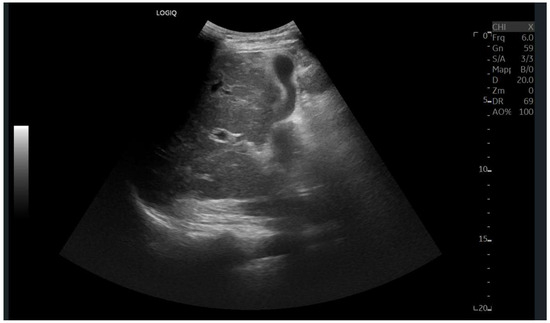

Abdominal ultrasound is a fundamental diagnostic tool in clinical practice, due to its availability, safety, and overall accuracy. This Special Issue will delve into the most recent technological and methodological innovations in abdominal ultrasound imaging, offering readers a comprehensive overview of advanced techniques, specific clinical indications, and solutions to emerging challenges. Among the various topics, it will cover the use of high-resolution probes, the integration of elastography for assessing liver fibrosis, and the application of contrast-enhanced ultrasound for identifying complex lesions. Strategies for training and professional development will also be examined to improve ultrasound performance and result interpretation.